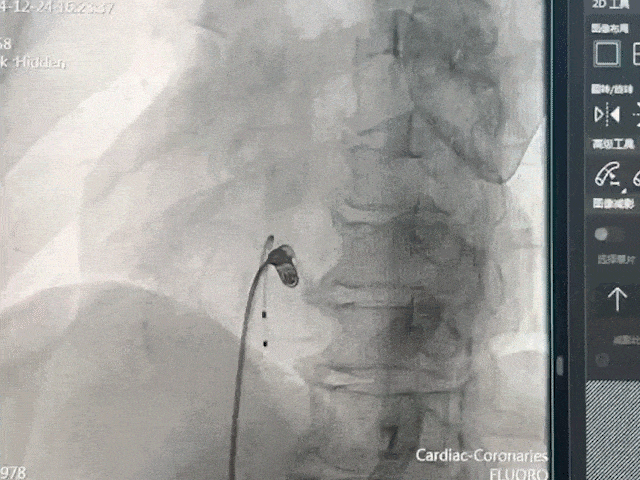

手术过程部分展示

猪尾造影,明确右室心尖、前室间沟、后室间沟、三尖瓣相对位置

将保护套筒送至下腔心房交界处